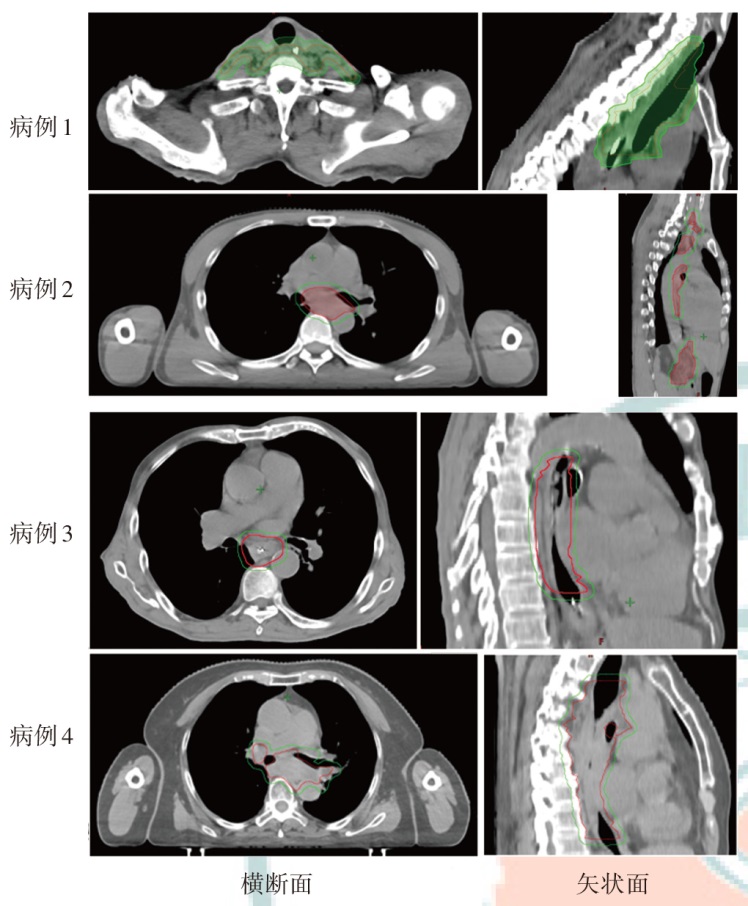

Objective To explore the dosimetric characteristics of proton radiotherapy plan and photon radiotherapy plan for esophageal cancer. Methods Four patients who were admitted to Shandong Cancer Hospital and Institute from January 2024 to April 2024 with esophageal cancer (cervical, middle thoracic and total esophageal tube, as well as the lymphatic drainage areas involved) and required radiotherapy were selected as the research subjects. Intensity modulated proton therapy (IMPT) and intensity modulated radiation therapy (IMRT) plans were designed respectively based on the clinical target volume and the dose constraints for organs at risk (OARs). Dosimetric parameters, including conformity index (CI), homogeneity index (HI), gradient index (GI) for target coverage, as well as OARs dosimetric parameters were evaluated. The volume of additional dose deposition in the body was compared by assessing regions receiving 10%, 30%, and 50% of the prescription dose. Results For all four cases, IMPT plans yielded lower HI values (0.12, 0.10, 0.06, and 0.08) than IMRT plans (0.15, 0.13, 0.10, and 0.11), and the GI values of IMPT plans (3.11, 3.21, 2.43, and 2.72) was lower than IMRT plans (4.52, 5.14, 3.09, and 3.92). Moreover, the CI of the IMPT plans (0.59, 0.60, 0.77, and 0.72) was inferior to IMRT plans (0.81, 0.77, 0.91, and 0.85). Compared with the IMRT plans, in the whole lung dose indicators of the IMPT plans for the 4 patients, V5 decreased by 34.1%, 55.0%, 79.7% and 60.3%, respectively; V20 decreased by 48.3%, 43.9%, 65.8% and 40.8%, respectively, and Dmean decreased by 43.4%, 57.2%, 76.2% and 45.4%, respectively. V30 of the heart decreased by 36.2%, 45.3%, 40.1% and 52.4%, respectively, and Dmean of heart decreased by 96.6%, 57.9%, 58.5% and 55.3%, respectively. For the middle and lower thoracic target area, the liver was significantly protected in the IMPT plan (Dmean decreased by 76.0% compared with the IMRT plan). In terms of the additional dose deposition in the patient's body, IMPT plans reduced the volumes receiving 10%, 30% and 50% of the prescription dose by 45.0%-61.4%, 41.2%- 61.8% and 34.8%-61.6%, respectively, compared with the IMRT plans. Conclusions By comparing the dosimetric parameters of IMPT and IMRT plans for 4 cases of esophageal cancer, the IMPT plans have advantages in reducing the doses to lung tissue, heart, and liver, and can also reduce additional dose deposition in the patient's body.